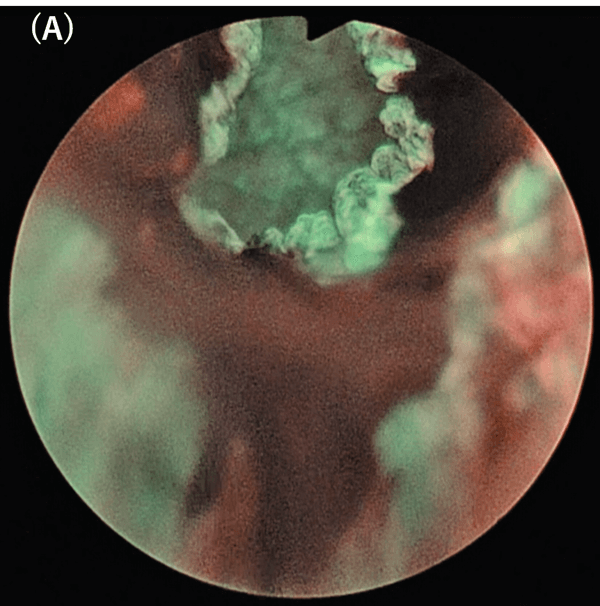

When there is a bleeding, the whole field of view becomes colored and unclear because NBI light bands are easily absorbed by hemoglobin (Fig. 6). Therefore, special attention is required during insertion of the cystoscope to avoid bleeding due to manipulation.

Fig. 6. NBI observations. (A) Bleeding from prostatic urethra by cystoscopic manipulation (posterior part is the bladder neck).